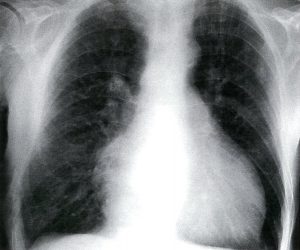

ایسکمی حاد اندام (ALI) یک اورژانس عروقی است که در آن خونرسانی شریانی به یک یا چند اندام به شدت کاهش مییابد. ترومبوز شریانی و آمبولی قلب مسئول اکثر موارد هستند. علائم و نشانههای معمول شامل درد، رنگ پریدگی، کاهش نبض، سردی، فلج و پارستزی اندام است که در قسمت دیستال به محل انسداد ایجاد میشود.